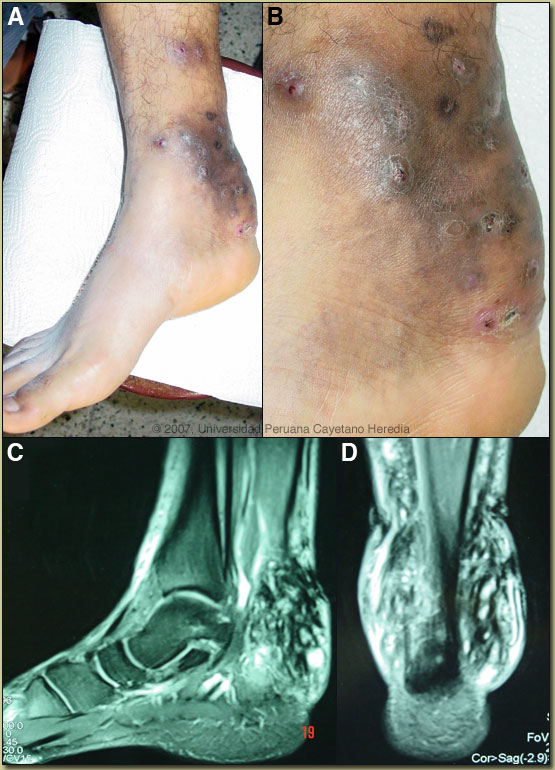

![]() History: 34-yo male with a 4-month history of painful swelling of the right foot, multiple draining papular lesions [Images A, B]. The fluid was gritty and bloody without purulence. No history of trauma, no similar history in contacts or colleagues, no fever or chills. Diabetic on metformin. Epidemiology: Fisherman, born in Chincha (250 km south of Lima) but resident in Lima for more than 13 years. Frequent sea trips all along the north shore of Peru. Physical Examination: Afebrile. Right foot as shown. Laboratory Examination: CBC and biochemistry were normal. Chest x-ray was normal. MRI of the right foot [Images C, D] showed an infiltrative lesion limited to subcutaneous tissue without any bony destruction or subluxation of small bones of the ankle.

Diagnosis: Mycetoma (madura foot syndrome) due to Phaeoacremonium inflatipes.

Discussion: White draining granular material grew Phaeoacremonium inflatipes. Culture for bacteria was negative. Excisional biopsy or invasive cultures of the sinus tracts are not usually necessary for diagnosis of madura foot as the granules usually come to the surface even if not on a daily basis. The main and important differential diagnoses in this case are TB, botrymycosis (chronic staphylococcal infection) [Gorgas Case 2003-04], actinomycosis [Gorgas Case 2001-09], other causes of chronic bacterial osteomyelitis, and malignancy. Madura foot is a common subcutaneous mycosis in the tropics and is caused by a wide variety of fungal organism. Madura foot typically presents in a similar way to this patient, with a small local tumor slowly progressing over years to more widespread destruction of subcutaneous tissue and bone while sparing nerve and vasculature. Etiologic agents of maduramycosis are divided into several groups:

Mycetomas appear to be localized phenomena due to local inoculation without any potential for widespread dissemination. Maduramycosis is most common in Africa, Central and South America, and the Far East. Most cases occur in tropical latitudes between 15 degrees South and 30 degrees North in humid moist environments. The organisms have been isolated from soil as well as from plant thorns. The identification of species of Phaeoacremonium based on their morphological and cultural characters is difficult [see detailed review in J Clin Microbiol. 2005 Apr;43(4):1752-67], as is evident from the numerous incorrect identifications that have been made since the genus was established in 1996. A reliable technique for Phaeoacremonium species identification is needed. At present 6 species have been associated with human disease but reports in the literature are scanty. ![]() In contrast to bacteria and actinomycosis (which is responsive to Penicillin), madura foot has been characterized as being poorly responsive to medical therapy, and aggressive surgery or amputation is commonly recommended. Although randomized controlled trials are not available, recent consensus from experts in highly endemic areas of Africa and the Americas indicates that 6-12 months of ketoconazole or itraconazole is very often successful in improving the lesions, even if complete cure is not achieved. In tropical countries, amputation or highly destructive excisional procedures in impoverished rural residents usually carriers a poor prognosis for rehabilitation and ongoing complications. Prosethetic appliances are not available. Because the infection does not disseminate and is non-painful, surgery should be used only as a last resort with widespread disease, weighing the benefits versus the above-mentioned adverse aspects of this kind of surgery in certain settings. Less than extensive disease can often be observed for several years even if drug therapy is not available. Our patient has received itraconazole 200 mg/d for 1 year with some improvement [Image E].